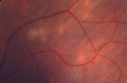

66 year old man with dense cataracts and recurrent uveitis. Starting 6 days ago and before that New Years Eve. The left eye has been treated since 11/2013 for iritis in the left eye. The patient was on Prednisolone drops. He weaned down completely off the drops and he was fine until New Years. He restarted the drops and the vision cleared until last Saturday. The attack was usual. He gets a lot of pain in the left eye and the eye is sensitive to the touch. His vision gets a little worse with the attacks. He has had episodes in each eye. He has a history of severe intermittent right knee pain and also has ulcers on his lower leg on both sides which are thought to be circulatory. VA OD: Dcc20/40 PH20/32-2 VA OS: Dcc20/200-2 PH20/63-1 Syphillis, Sarcoid, TB, Birdshot Negative except for slightly elevated Lysozyme and normal ACE Dentist found cyst which was biopsy positive for sarcoid 6 months later.

Sarcoidosis Multifocal Choroiditis505 views66 year old man with dense cataracts and recurrent uveitis. Images show multifocal choroidal granulomas from sarcoidosis more in the right eye than the left eye.00000